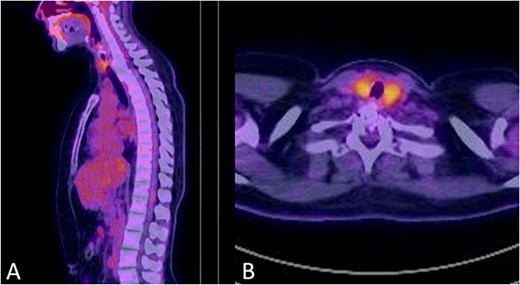

There were no surgical complications intraoperatively or postoperatively. A 3-day postoperative X-ray determined there was no mispositioning of the VBR and instrumentation (Fig. 3). There were no inpatient medical complications and pain was managed appropriately. Patient was discharged from hospital shortly after the operation and recovery. As outpatient, she did not complain of pain or wasn’t immobilized outside of the hospital. A 15-month follow-up MRI and 30-month follow up Positron emission tomography–computed tomography (PET-CT) maintained to show that the patient was tumour free (Figs 4 and 5). Lastly, upon assessment in clinic over 30 months, the patient was fully mobile and self-reported to be pain free, living independently and comfortably. There were no hardware related issues and there wasn’t any development of infection.

A 15-months postoperative follow up MRI Scan in May 2021. (A) Sagittal view of VBR cage indicating tumour free T2 body. (B) Transverse view of spinal compression reduction and resolved ESCC score.